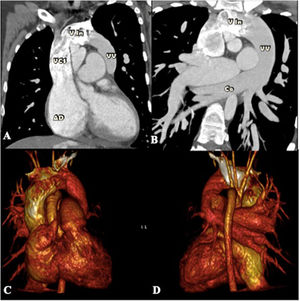

En nuestro caso presentamos a una paciente de 30 años, sin intervenciones previas, con antecedentes de acropaquias desde los 6 años, sin otro síntoma. Fue derivada a nuestra institución con historia de disnea de medianos esfuerzos, palpitaciones, dolor torácico y deterioro de la clase funcional de 2 meses de evolución. En la radiografía de tórax se observó flujo pulmonar aumentado y cardiomegalia a expensas de las cavidades derechas, imagen en «muñeco de nieve» (fig. 1). En el ecocardiograma se evidenció conexión anómala total de venas pulmonares variedad supracardíaca a través de una vena vertical sin obstrucción, comunicación interauricular tipo ostium secundum, dilatación de cavidades derechas y presión sistémica estimada de la arteria pulmonar de 69mmHg. Se complementaron los estudios con tomografía computarizada por sospecha de tromboembolismo pulmonar, donde se encontró drenaje anómalo de todas las venas pulmonares derechas, las del lóbulo inferior y lingulares izquierdas, las cuales confluyen en un colector común horizontal, las venas pulmonares del lóbulo superior izquierdo confluyen en la unión del colector horizontal y longitudinal. Posteriormente, por medio del colector longitudinal izquierdo drenan a la vena innominada, y esta en la cava superior, desembocando en la aurícula derecha (fig. 2). Se descartó tromboembolismo pulmonar y trombosis venosa profunda en las extremidades inferiores. Se sometió a cateterismo cardiaco por vía femoral derecha, donde se determinó salto oximétrico en la vena cava superior y desaturación sistémica con relación a la vena pulmonar (aorta-PaO2: 53mmHg, SaO2 90% vs. vena pulmonar-PaO2: 87mmHg, SaO2 98%). En levofase el retorno venoso pulmonar derecho e izquierdo va hacia un colector, que desemboca en la vena vertical-innominada y posteriormente desemboca en la vena cava superior, con opacificación del atrio derecho y paso de medio de contraste al atrio izquierdo (AI) a través de un defecto septal auricular (fig. 3).

Tomografía computarizada con: A) imagen de reconstrucción multiplanar mostrando conexión de vena vertical a vena innominada; B) imagen de la confluencia de venas pulmonares al colector venoso, con posterior drenaje a la vena vertical; C) reconstrucción tridimensional sagital derecha; y D) reconstrucción tridimensional sagital izquierda mostrando el colector venoso a la izquierda de arco aórtico y que desemboca en la vena innominada y posteriormente a la vena cava superior.

AD: aurícula derecha; Co: colector venoso; VCS: vena cava superior; Vin: vena innominada; VV: vena vertical.